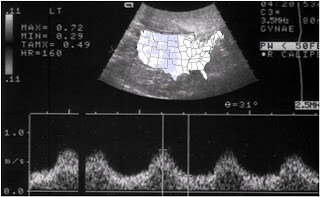

We’ve had a big couple of days too. In addition to packing for 7 nights ‘o camping fun, I also went to an ultrasound yesterday AND we went to the park this morning so Mia and the boys could meet for the first time. The ultrasound was amazing yesterday. It’s definitely different being a spectator and not the one experiencing the warmish goo-gel slide across your belly. There’s still something very surreal about the whole experience and I know that really, until that baby is in our arms and coming home with us, it won’t sink in that this is all happening. Baby right now weighs 2.5lbs. (at 26 weeks) which is awesome considering when I went into preterm labor with Zachary at 28 weeks he JUST weighed 2.5lbs. Mia will likely have no problem growing this baby – apparently Mia and her half-siblings were all BIG babies. Mia’s 7 year-old half-sister weighed TWELVE (yes, 12) pounds. The doctor actually induced Mia’s mom lest she end up having a 15 pound baby. AND this amazing/crazy/poor woman had all of her children naturally! (I didn’t do that and my bebes were only five pounds! Really, I shoulda/coulda just sneezed ‘em out).